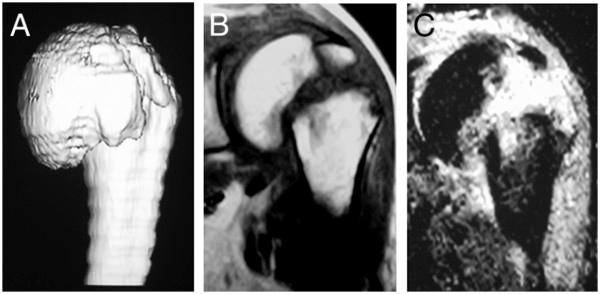

A 53-year old postman suffered from shoulder dislocation with an undisplaced fracture of the humeral anatomical neck which was initially undiagnosed. After the first attempt to reduce the dislocation of the shoulder joint by Stimson's method, complete displacement of the fractured humeral anatomical neck occurred. By closed reduction under general anesthesia, the displaced humeral head was successfully reduced and was subsequently treated by conservative therapy using sling immobilization. Follow-up by MRI two years later showed no evidence of avascular necrosis of the humeral head. The patient showed a satisfactory range of motion of the affected shoulder joint.In the present case, the blood supply was partially preserved because a part of the lesser tubercle remained attached to the displaced humeral head.

一名53岁的邮递员,患有肩关节脱位,伴有肱骨解剖颈无移位骨折,最初未被诊断出来。在首次尝试通过斯廷森法复位肩关节脱位后,肱骨解剖颈骨折出现了完全移位。通过全身麻醉下的闭合复位,成功复位了移位的肱骨头,随后采用吊带固定进行保守治疗。两年后的MRI随访显示,没有肱骨头缺血性坏死的迹象。患者患侧肩关节的活动范围令人满意。在本病例中,由于部分小结节仍附着于移位的肱骨头,血供得以部分保留。